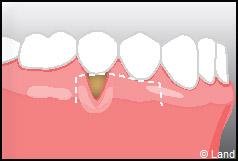

LES TECHNIQUES SANS APPORT DE GENCIVE :

Elles font appel à des lambeaux de gencive restante à proximité des récessions, qui sont déplacés et repositionnés sur la récession.